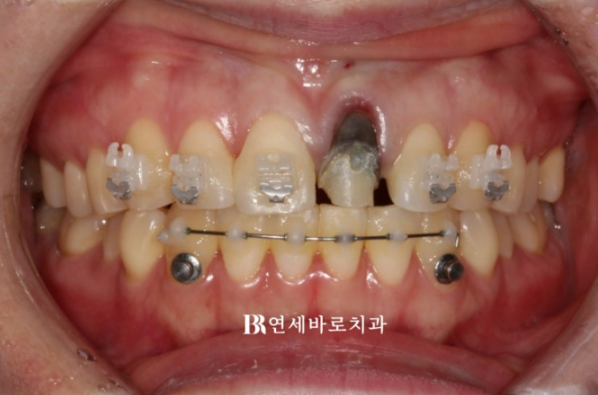

윗니에는 치아 뿌리까지 움직이기 수월하도록 클리피씨 장치를, 배열이 삐뚠 아랫니에는 부분교정용 MTA 장치를 붙여서 교정을 시작했습니다.

부러진 치아에 임시치아를 씌운 상태로 클리피씨를 붙이고 교정을 진행합니다.

보통 치아를 잇몸뼈로부터 정출 시키면 잇몸도 같이 따라 내려옵니다.

그래서 6개월 후 사진의 파란 화살표를 보면 잇몸이 치아와 함께 아래로 많이 자라 내려오면서 처음에 비해 치아가 절반정도로 짧아져 보입니다.

23.05

잇몸섷영을 해서 과하게 자라 내려온 잇몸을 제거했습니다.